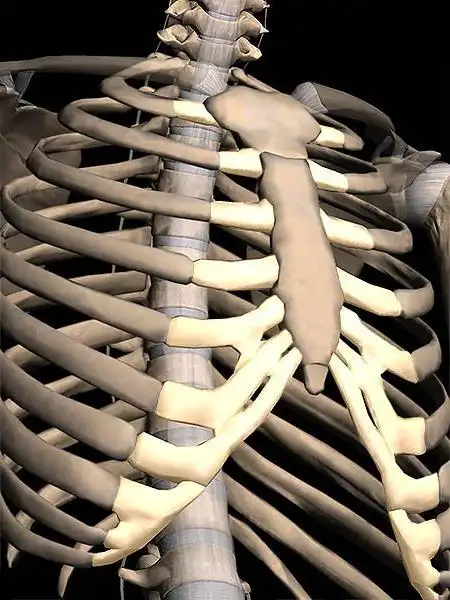

求解剑突疼是怎么回事

胸剑突

胸骨剑突增加如何呢